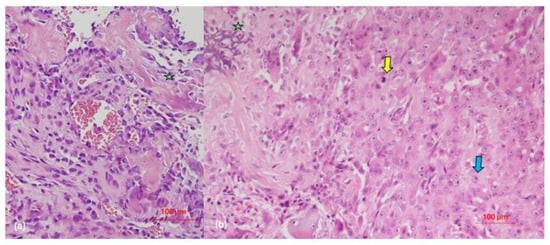

3.2. Pathological Characteristics of Tumor Lesions

| Case | Histological Morphology | Grade | Broder’s Classification | Soft-Tissue Involvement | Lymphovascular Invasion |

|---|---|---|---|---|---|

| 1 | Fibroblastic | High | Grade 3–4 | No | No |

| 2 | Chondroblastic | High | Grade 3 | No Yes (after recurrence) | No Yes (after 3rd recurrence) |

| 3 | Epithelioid | High | Grade 3 | Yes | No |

| 4 | Osteoblastic | High | Grade 4 | No | No |

| 5 | Osteoblastic | High | Grade 3 | Yes | No |

| 6 | Chondroblastic | High | Grade 2–3 | Yes | No |

| 7 | Osteoblastic | High | Grade 4 | No | No |

| 8 | Epithelioid | High | Grade 4 | No | Yes |